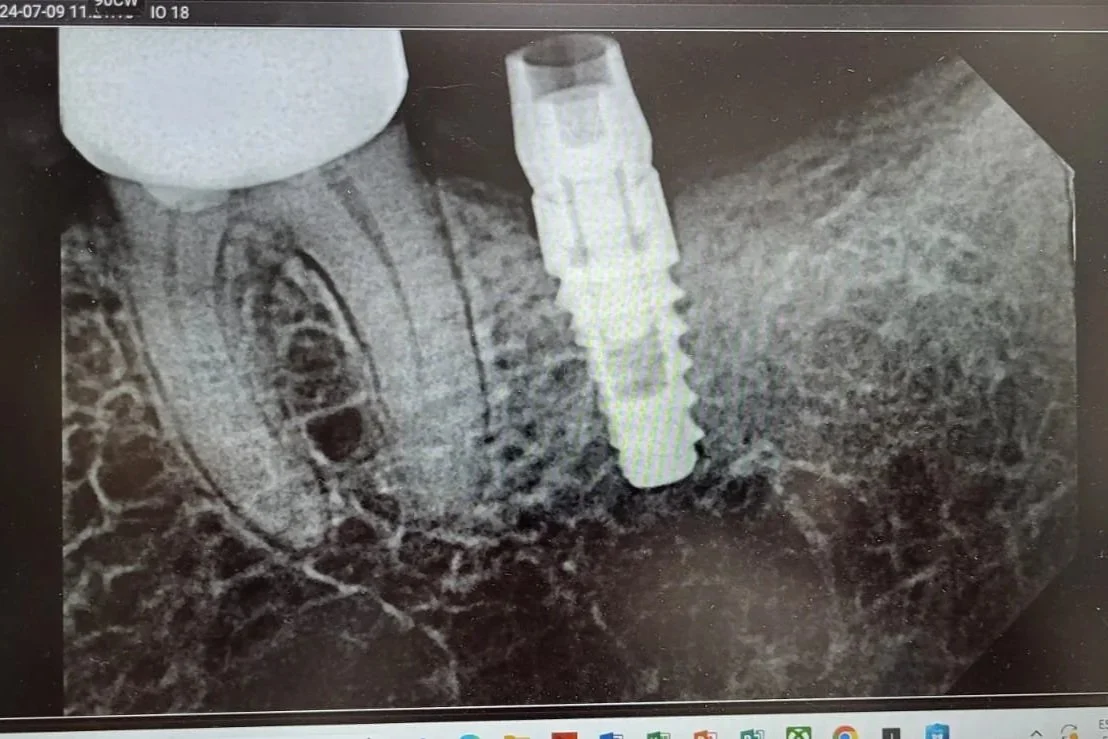

X- rays

Dental X-rays (radiographs) are images tools used by the dentists to visualize the teeth, gums, implants and the surrounding bone structures. They play a crucial role in diagnosing dental issues that may not be visible during a routine examination, like cavities, tooth decay and impacted teeth.